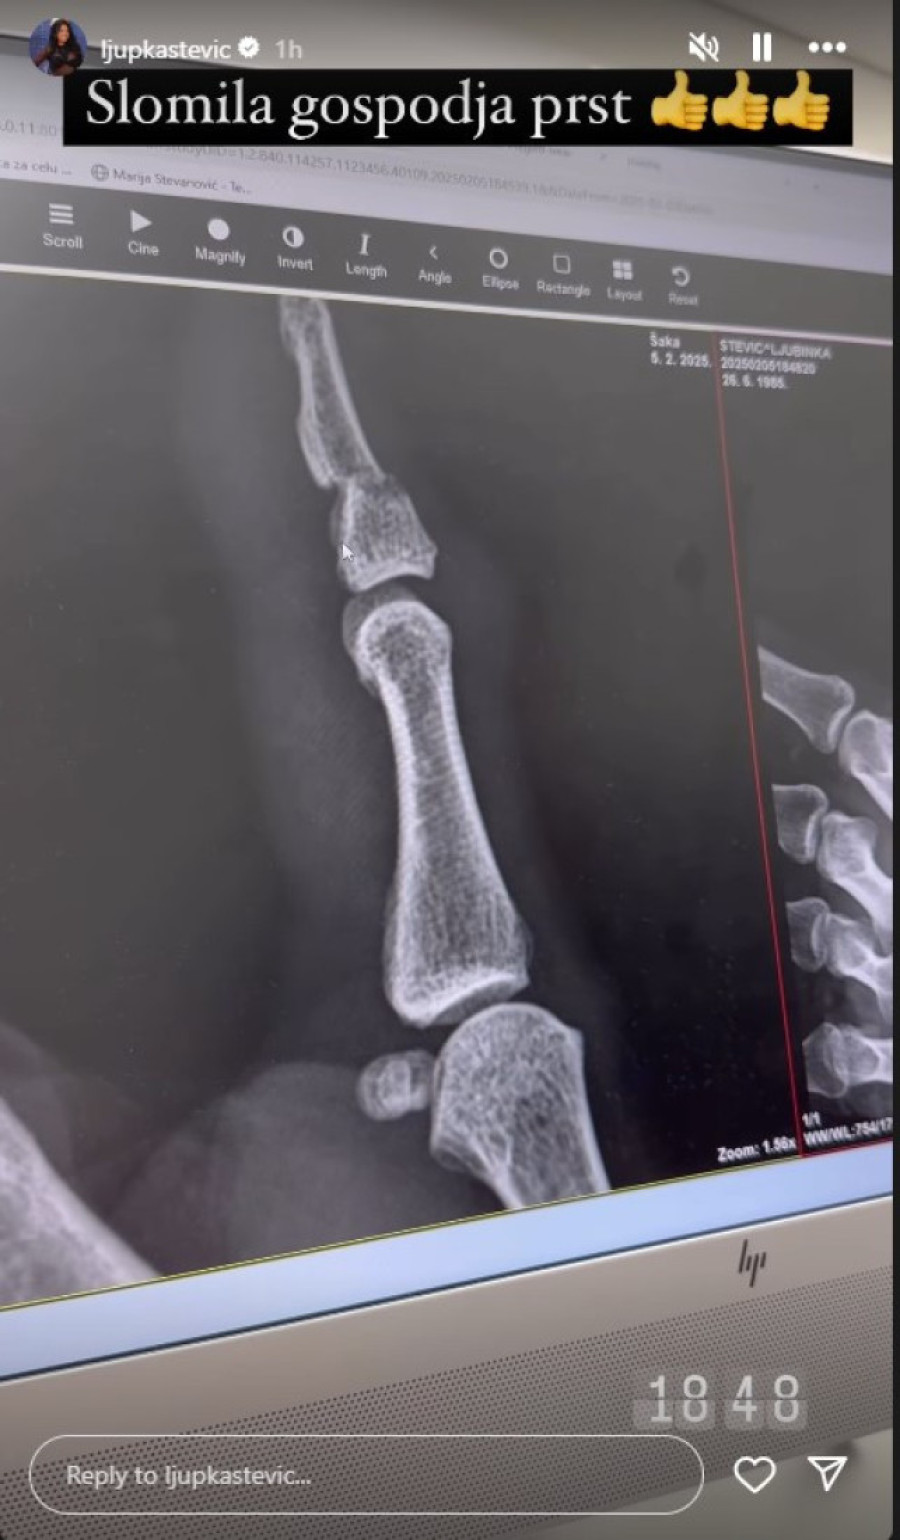

Ljupka Stević je podelila sa javnošću, putem svog naloga na Instagramu, da je doživela povredu.

Kako je otkrila, ona je polomila prst, tačnije palac. Stevićeva je otišla da povredu snimi i da joj lekari saniraju povredu, a potom je, dok je bila u kolima, pozvala roditelje da im ispriča šta se desilo.

- Palac sam slomila, ispod nokta je prelom. Zalupila sam samoj sebi vrata od auta - ispričala je Ljupka ocu, a onda je pozvala i majku: